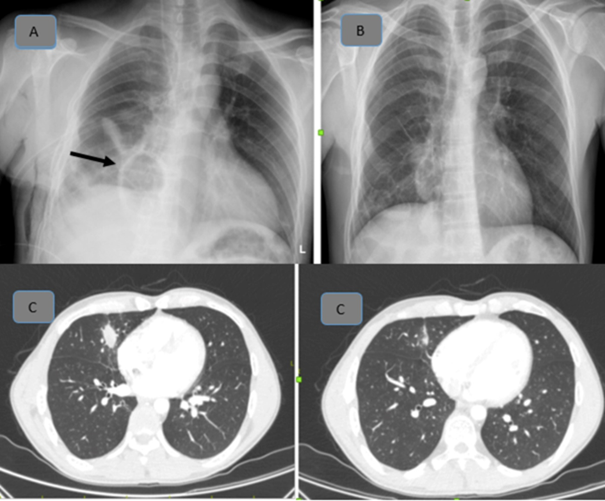

A 34-year-old male patient presented to the emergency department following a motorcycle accident resulting in multitrauma. Despite an unstable general condition, vital signs remained stable. The patient underwent multidisciplinary evaluation, revealing liver and spleen injuries, right hemopneumothorax, diffuse subcutaneous emphysema, and large traumatic cysts in the right lung (Figure 1). Additionally, fractures of the right 4th, 5th, 6th, and 7th ribs, right scapula, proximal humerus, and right olecranon avulsion fracture were identified through imaging studies. Immediate right tube thoracostomy was performed in the emergency room, followed by surgical intervention by the general surgery team and completion of orthopedic treatments. Subsequent to tube thoracostomy, due to minimal drainage, absence of significant air leakage, and radiographic confirmation of lung expansion within the right hemithorax, a decision was made for conservative management with close observation. Following approximately two weeks of intensive care unit monitoring, the patient was transferred to the ward. Chest tube removal was conducted in the ward, and the patient was monitored for an additional hour. Sequential posteroanterior (PA) chest radiographs taken at regular intervals revealed a reduction in size of the giant cysts with fluid accumulation. Upon stabilization of clinical status, the patient was discharged. Subsequent outpatient clinic evaluation two months later demonstrated regression of the giant cysts on thoracic CT imaging (Figure 2A–2C).

Figure 1 Posttraumatic thorax CT and traumatic pulmonary pseudocysts.

Figure 2A PA radiograph taken at the 2nd week of follow-up (black arrow: pseudocyst).

2B Control PA radiograph taken 2 months later.

2C Thorax CT taken at the 2nd month.